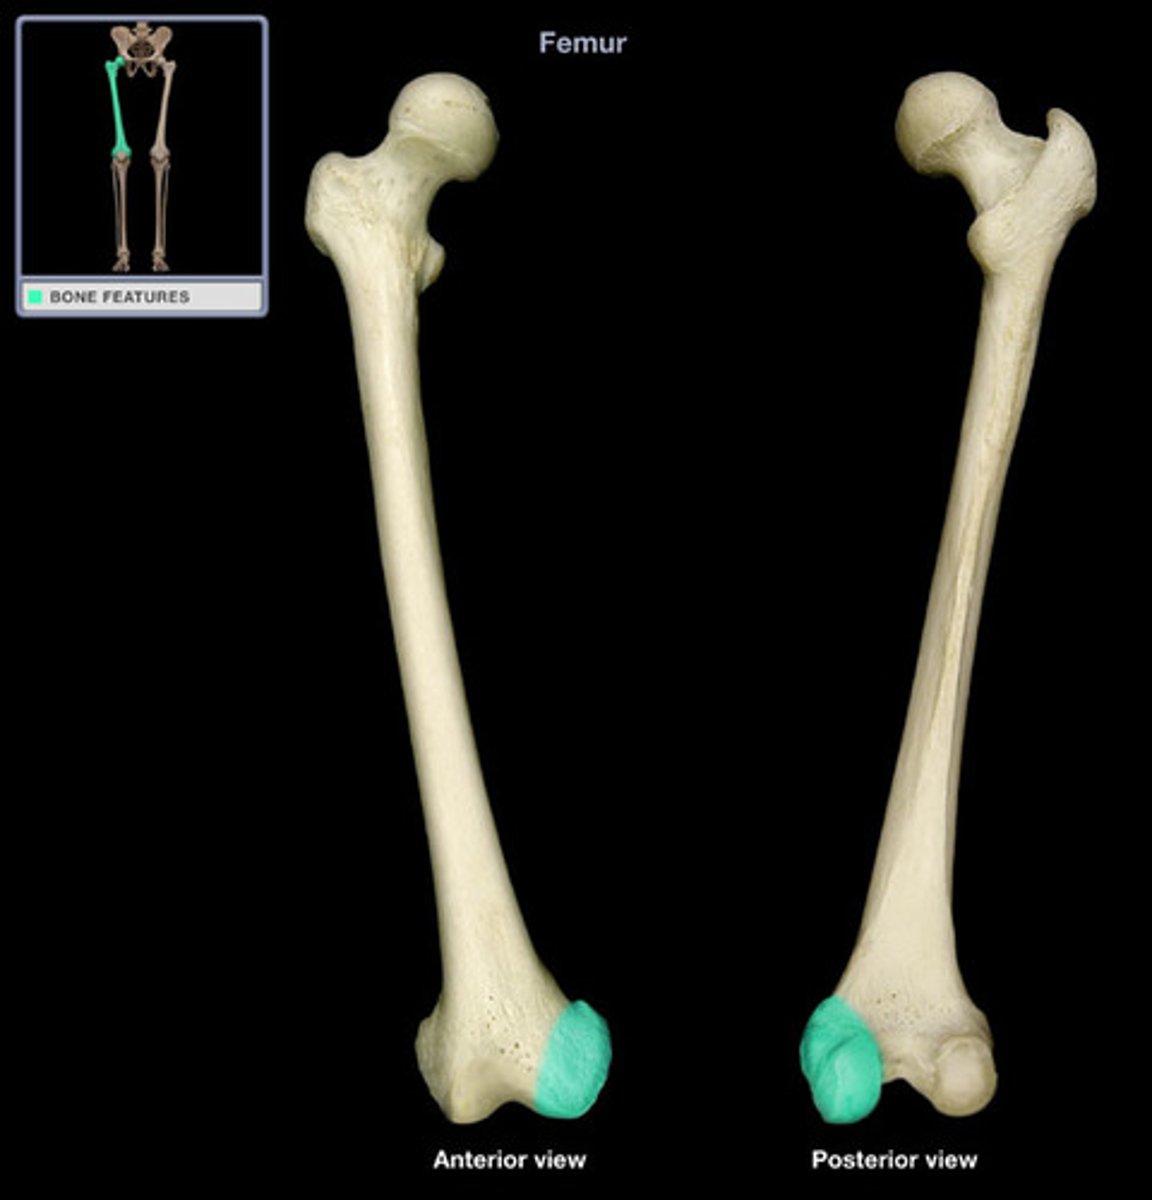

greater trochanter

Lesser trochanter

gluteal tuberosity

Lateral condyle

inferior to the epicondyle

Medial condyle

adductor tubercle